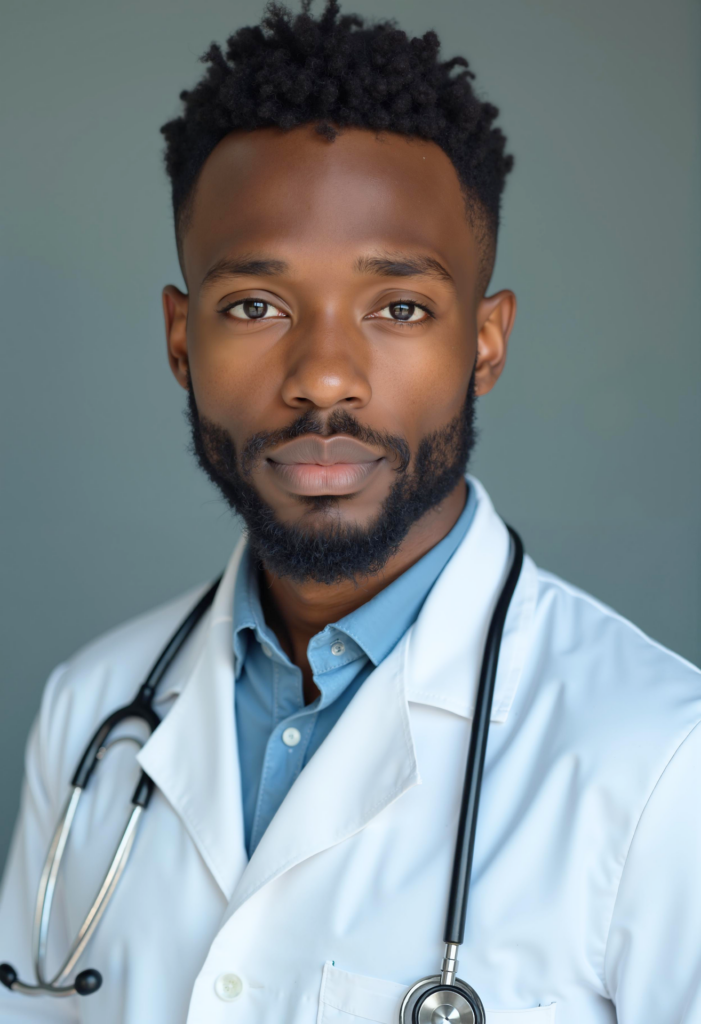

Cabinet dentaire